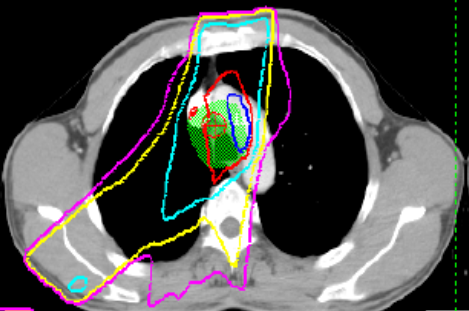

典型RILI影像表现及射野

WUj2fvhRjYOMcNYU.jpg EUuSa662a6s4XYS0.jpg